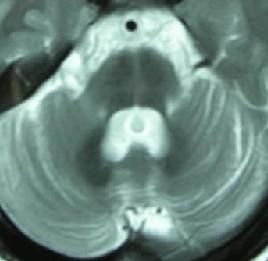

MRI或CT檢查顯示腦幹小腦有不同程度的體積縮小,腦池、腦室有不同程度的擴大及大腦皮質腦溝增寬等也可表現為正常。

夏伊-德雷格綜合症結果: 3例SDS患者均為隱襲性發病,初次就診距發病時間為2~6年,平均4年。3例均有頭暈、尿頻症狀,其中2例有尿瀦留、尿失禁、陽萎和便秘,1例並有暈厥。3例均有直立性低血壓,臥、立位收縮壓下降45~70mmHg(1mmHg=0.133kPa),平均下降58mmHg,舒張壓下降15~25mmHg,平均下降20mmHg。3例均有行走不穩,共濟失調和龍貝格征陽性及下肢單側或雙側巴賓斯基征陽性和查多克征陽性,植物神經檢查,2例患者胸3、4以下皮膚乾燥、無汗,雙下肢皮膚劃痕試驗白色明顯延長,1例患者手足及軀幹皮膚乾燥、皸裂,指甲粗糙。全部行頭顱MRI掃描,2例有腦幹及小腦萎縮,1例行P300檢查潛伏期延長P3b412ms,3例患者行SSR下肢檢查,1例SSR未測出,另2例SSR波幅低限(0.1μV,0.12μV)結果全部異常。